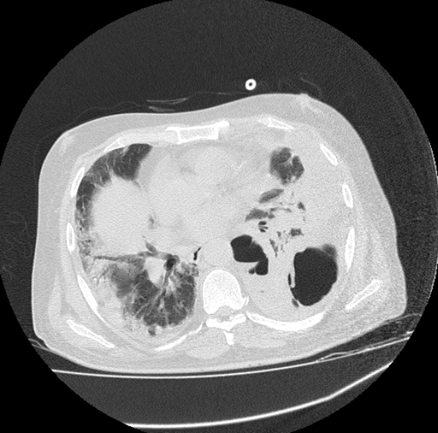

The above image also reflects the presence of ground-glass opacity along with air bronchogram which increases difficulty of breathing to the patient. This stage reflects the presence of pulmonary consolidation in patient’s lungs, which may proceed if immediate treatment is not provided to the patient. The increase in this consolidation means difficulty in breathing, which also show some symptoms like fever, fatigue, and severe cough. (Figure 4)

Figure 4 CT Imaging reflecting presence of Air Bronchogram.